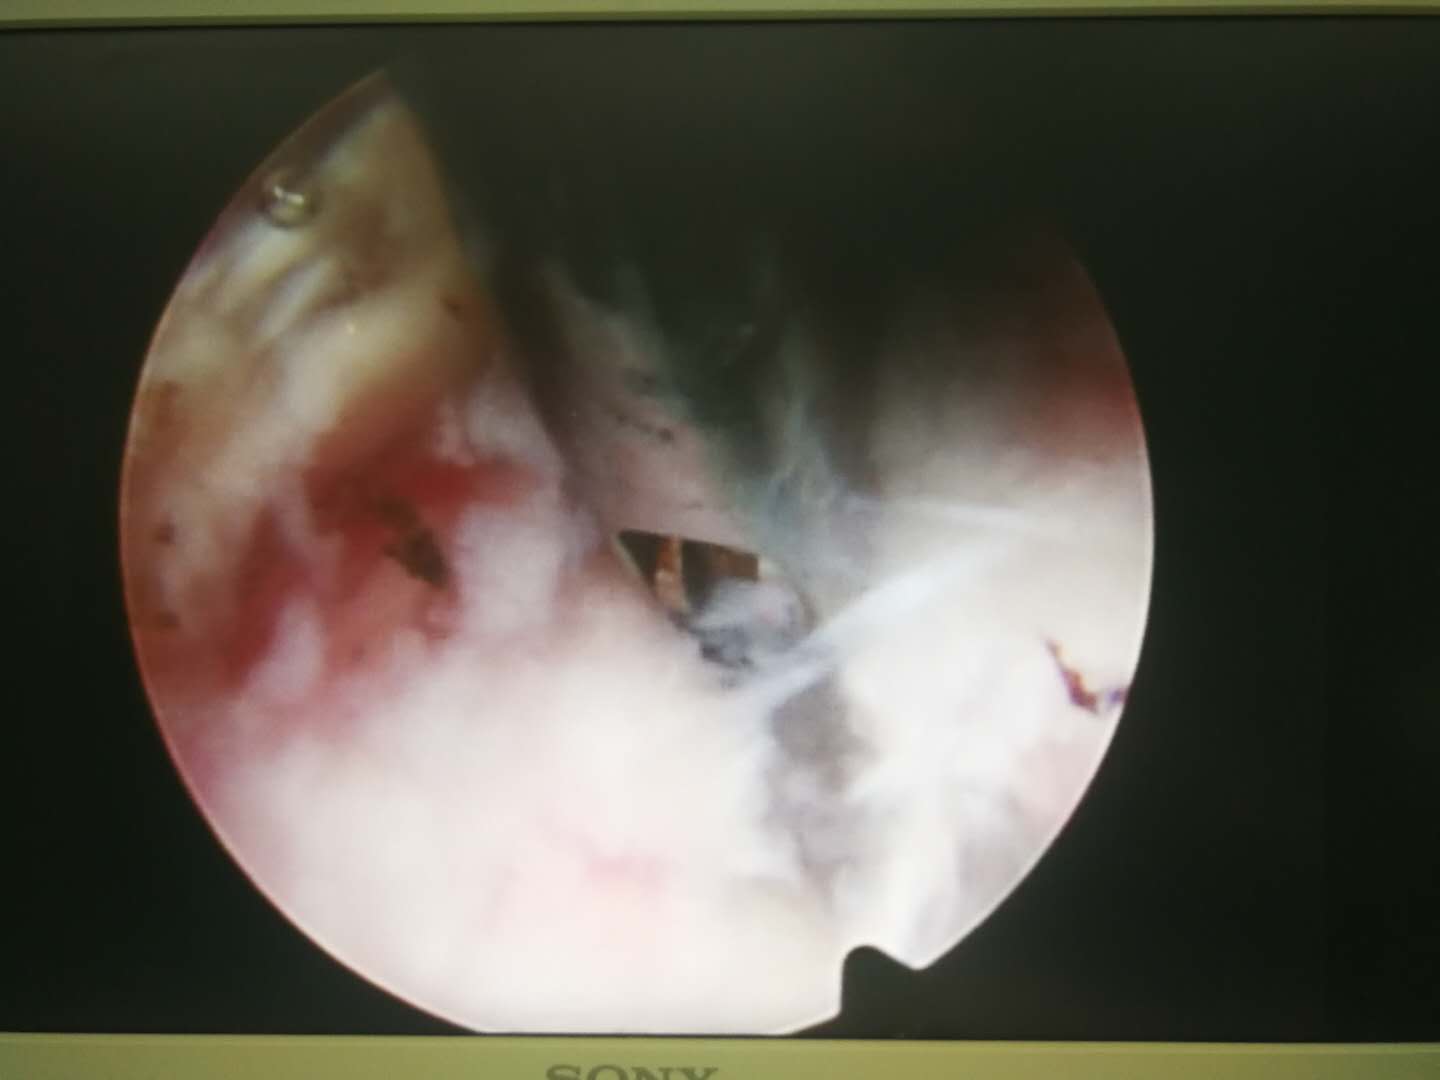

12月30日,我院骨五科医疗团队成功完成一例经皮椎间孔镜上腰椎极外侧间盘突出切除术。这一手术的成功开展,标志着我院在脊柱外科领域的微创治疗技术又上了一个新台阶。 患者高先生8年前曾因下腰椎腰4-腰5、腰5-骶1椎间盘突出,于我院骨五科行腰4-腰5、腰5-骶1椎板减压+椎间盘切除+椎间植骨融合术,为其解除了病痛。4年前患者行腰椎内固定取出术。半年前患者无明显原因再次出现腰部疼痛,咳嗽时尤为明显,遂再次求诊与我科。我院骨五科主任钱宏主任医师组织科室医疗团队,经过对患者的详细查体和相关影像学检查,诊断为由腰椎融合术后退变引起的上腰椎(腰2)极外侧间盘突出症,突出的椎间盘压迫出口神经根,导致患者再次出现腰部和腿部疼痛。 考虑到高先生既往曾经历过两次传统脊柱切开手术,如果再次运用该手术来切除突出的椎间盘,对其自身的脊柱解剖结构损伤比较大,会影响到脊柱的稳定性,日后的生活质量也会受到较大的影响。我院骨五科主任钱宏主任医师组织科室医疗团队,多次讨论手术方案、反复评估手术效果,最终决定为高先生实施经皮椎间孔镜上腰椎极外侧间盘突出切除术。 在征得高先生及其家属的同意后,钱宏主任带领科室医疗团队成员高炬、朱步奇、王海蛟医师,在局麻下利用穿刺针,经病变椎体后外侧穿刺至椎间孔处,在扩大椎间孔及神经根管后,建立了手术微创通道,并通过该通道对其突出的椎间盘实施了切除。 术后,高先生的恢复状况良好,腰间也仅留下了一个1厘米左右的伤口,“手术过程中,我就明显感觉自己的症状在减轻,腿也不那么麻了。术后第2天,就可以下床行走,还能自己去上厕所。”高先生满意地介绍说。 经皮椎间孔镜技术,是脊柱外科领域典型的微创手术,相对于传统的脊柱切开手术,该手术切口小,对患者脊柱的解剖结构基本上无损伤,最大程度地保护了脊柱后方软组织,还大大减少了医源性并发症的发生,提高了手术的安全性。患者术后康复时间短,基本不影响其的日常生活。据介绍,该技术还能应用于部分颈椎间盘突出疾病的治疗,为更多的患者带来了健康的福音。 我院骨五科主任钱宏主任医师组织其科室医疗团队成员高炬、朱步奇、王海蛟医师,前往中国人民解放军总医院(301医院)、北京积水潭医院等地进修学习,现已熟练掌握了该项技术,目前已成功开展多例该项手术,为患者解除了病痛。

镜下操作 切除的突出椎间盘